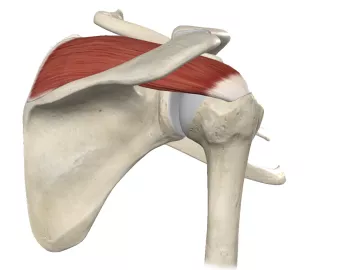

Rotator cuff issues can vary from mild strains to severe tears, posing treatment dilemmas. Massage can play a key role in conservative treatments if the therapy is well-designed and targeted to the client’s individual presentation.